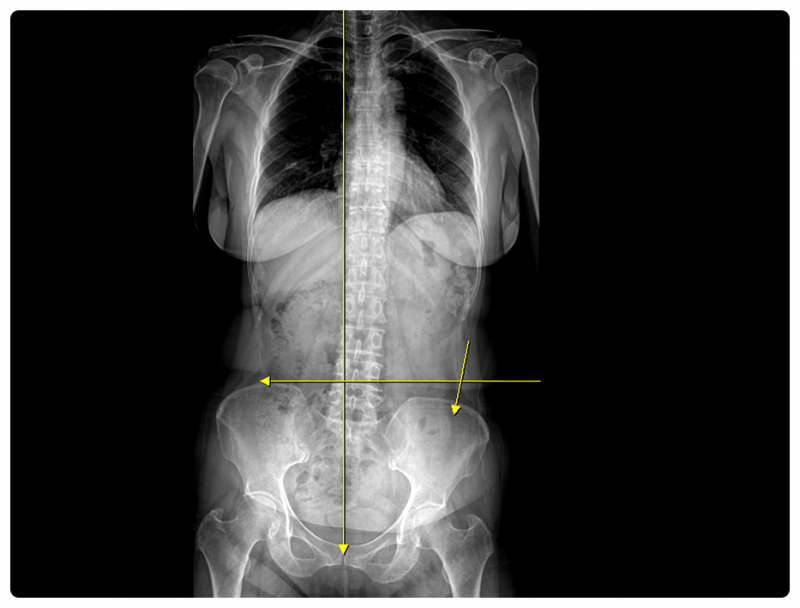

무릎 관절 자체의 문제가 아니라 발목 정렬이 틀어져 있거나, 골반이 한쪽으로 기울어지며 부담이 누적된 경우도 적지 않습니다.

그래서 저는 통증이 있는 부위만 살피기보다, 원인이 되는 ‘가해자’가 어디에 있는지부터 찾는 과정을 중요하게 보고 있습니다.

그래서 동래도수치료 등을 진행할 때에도 뼈의 정렬뿐 아니라 근육 상태, 신경 자극 여부, 자세와 동작까지 함께 고려합니다.

여러 검사와 확인을 통해 원인을 찾고, 통증과 불균형을 함께 다루는 것이 목표입니다.

겉으로 드러난 증상뿐 아니라, 그 안에 숨어 있는 이유까지 함께 살펴보는 접근이 필요합니다.